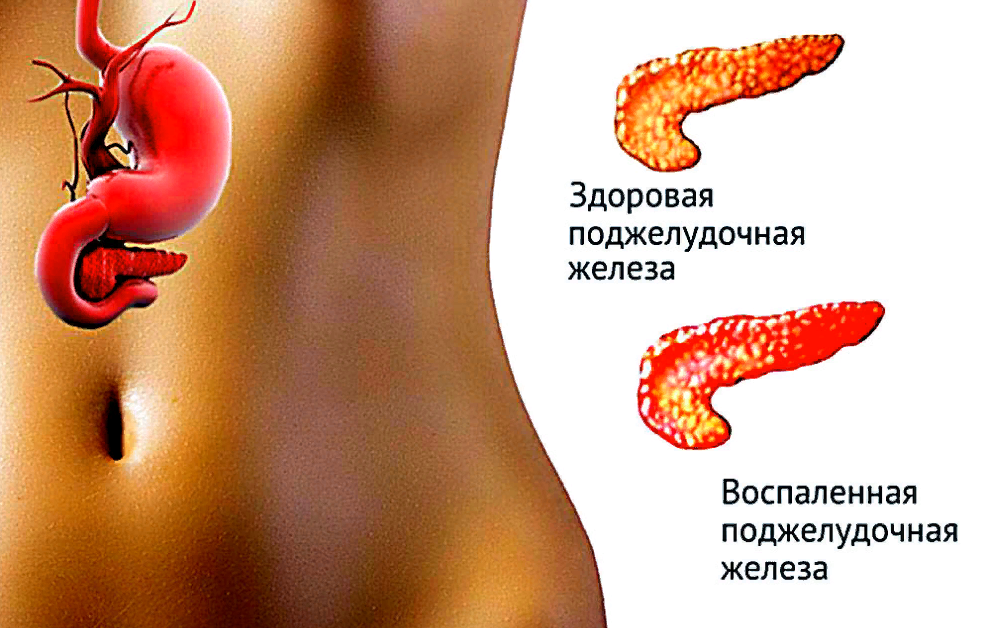

Как лечить – скажет врач. Самолечение здесь может только навредить. Боли в поджелудочной железе говорят о том, что в ней началось воспаление. Такое заболевание называется панкреатит. Для его начала должны быть весомые причины, чтобы в поджелудочной образовалось воспаление.

Панкреатит хронической формы дает меньше боли, чаще всего после погрешности в еде. Его опасность заключается в развитии опухоли самой ПЖ, отечности соседних тканей. В это время важно не пропустить рост злокачественных новообразований.